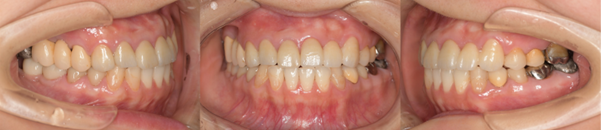

インプラント症例1

Before

インプラント症例1 治療前

After

インプラント症例1 治療後

年齢・性別

30代 男性

治療動機

「入れ歯が合わない。被せ物が取れた。結婚式までにインプラントにしたい。」とのことでした。

病歴

間食が多く、むし歯により欠損多数。入れ歯が入っていました。残存歯もむし歯になっていました。歯周病は罹患ありませんでした。

治療内容

喫煙習慣があったので、禁煙していただきました。患者様は大変熱心に習慣の改善に努められました。

上顎は全ての残存歯でむし歯が大きく、保存不可能でしたので抜歯して無歯顎状態にし、臼歯部は顎堤の委縮が著しかったためサイナスリフトを両側に行い、10カ月待機後、8本のインプラントを埋入し、7カ月待機後チタンとジルコニア製の上部構造を装着しました。

左下4、5歯は、上顎手術の待機期間を利用して治療を行いました。むし歯のため保存不可でしたので抜歯と同時に骨造成を行い、骨の治癒を待った後、左下4、6部に2本インプラントを埋入し、ブリッジタイプの上部構造を装着しました。

右下の臼歯もむし歯の為、本来は抜歯しなければならないのですが、患者様のご都合により、保存しています。

治療期間

約17ヶ月(抜歯からインプラント上部構造装着まで)

治療費概算

上顎約650万円、下顎171万円(いずれも消費税込み)

治療後の状況

無事に結婚式までに治療を終えることができました。見た目が大幅に改善されたこと、入れ歯に比べて噛みやすく、脱離もしないことを大変喜んでいただきました。インプラント周囲炎予防の為、患者様には口腔内清掃を毎日頑張ってもらっています。それから1〜3か月ごとにプロフェッショナルケアを行っています。

治療の注意事項

睡眠時の歯ぎしりや日中のくいしばりがあると、気づかないうちに歯やインプラントへ過剰な力がかかります。継続して歯や歯ぐきの状況を確認していくことが重要です。